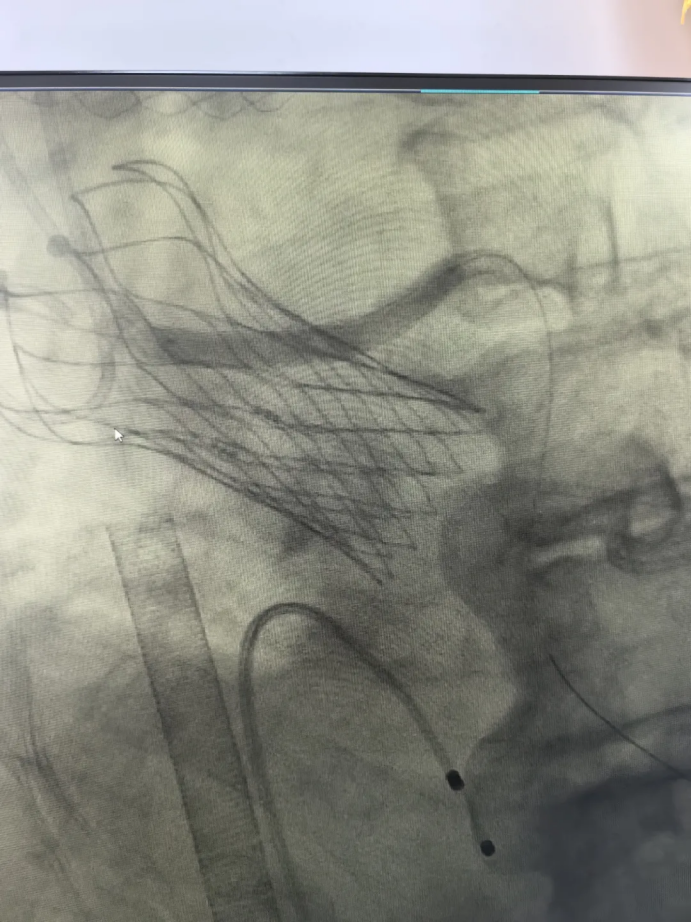

心血管内科林力扬介入团队经过细致术前评估、术前分析和反复讨论,并充分做好各种预案后,治疗方案也得到了老人及家属的认可。团队决定于2025年10月13号为老人行TAVR手术。10月13日,林力扬副主任医师、林建粦主治医师在介入导管室会同福州大学附属省立医院郭延松心脏瓣膜介入团队,凭借着丰富的经验和高超的技术,在体外膜肺氧合(ECMO)支持下,顺利通过导管将人工心脏瓣膜精准地输送到病变部位,成功完成了主动脉瓣瓣膜置换,并完成冠状动脉左主干烟囱支架植入术,方大爷安返病房。

术后在ICU监护两天后,方大爷恢复良好,主动脉瓣跨瓣压差从术前的82mmHg降至6.5mmHg(正常值<20mmHg)。转到心血管内科普通病房,经过医护人员数日的精心照料,方大爷顺利出院。